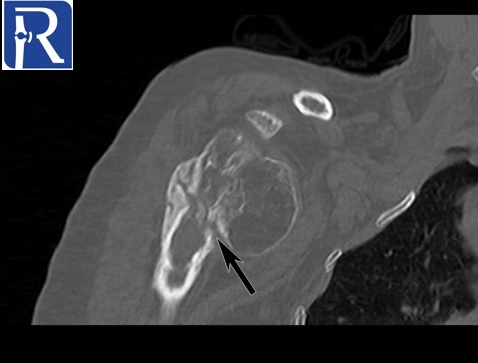

Demographic and clinical details: 70-years-old female patient, admitted with right shoulder pain and restricted motion.

Image Details: AP X Ray shows the inferior glenohumeral joint dislocation with non-united neck fracture (yellow arrow=. Note also deformation of humerus head (black arrow) and glenoid (white arrow). You can notice also superior cortical compression of humerus head consistent with hill sachs lesion. These findings are better seen on CT images.